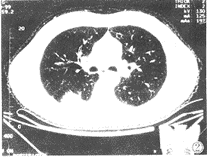

單側或雙側肺散在不規則斑片狀浸潤陰影,可融合成實變,其中有不規則透亮區,亦可伴有胸腔積液。病變蔓延到肋骨和脊椎時,可見到骨膜炎徵象,肋骨或脊椎破壞。

3.胸部X線檢查:肺內散在不規則浸潤影,可融合成大片實變,內有透亮區。

其他輔助檢查:X 線表現為支氣管肺炎,肺實變,其間有多個小透光區。亦可表現為團塊狀陰影,若經血行播散,則表現為肺內粟粒性病變。晚期有肺纖維化、胸膜增厚。

肺放線菌病討論患者以咳顆粒狀物及胸膜多髮結節為特徵,咳出物塗片找到典型的硫磺顆粒,故可確診肺放線菌病。放線菌病是由放線菌屬中的伊氏放線菌等引起的一種慢性化膿性肉芽腫性疾病,有瘺管形成並流出帶硫磺顆粒的膿液,發病率極低。該病好侵犯結締組織,組織病理改變主要為化膿性肉芽腫,膿腫中可見放線菌顆粒,顆粒外周為上皮樣細胞,巨噬細胞等,再外則為纖維組織。該病從臨床表現可分為面頸部型,胸部型和腹部型。胸部型可累及肺、胸膜、縱隔或胸壁,形成膿腫或咳出帶有硫磺顆粒的膿痰,伴發熱、胸痛和胸悶。胸片及CT所見無特異性,可類似肺炎、肺膿腫或腫瘤。確診要依靠真菌檢查,發現硫磺顆粒才有意義。治療首選青黴素,磺胺、紅黴素等亦可。治療深部放線菌感染時,宜大劑量,長療程,一般靜脈滴注青黴素1 000~2 000萬u/d,2~6周,然後口服青黴素2~4g/d,3~12個月或更長。